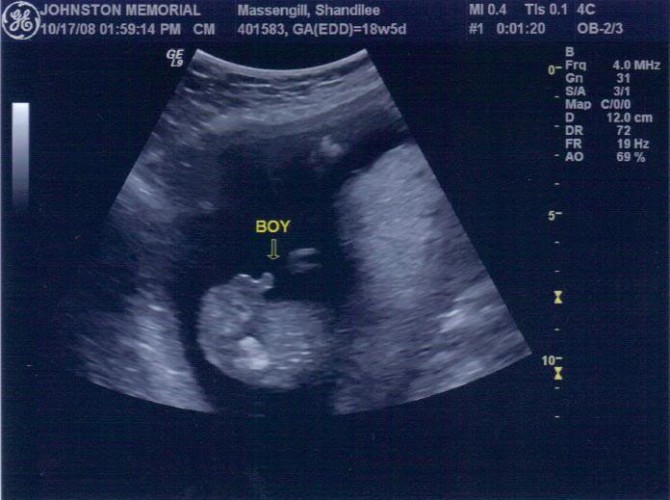

Важно: в 22-24 недели УЗИ позволяет установить пол малыша. Иногда, узнать мальчик у вас будет или девочка, можно еще в первом триместре. Если вы не хотите знать пол ребенка до рождения – заранее предупредите диагноста!